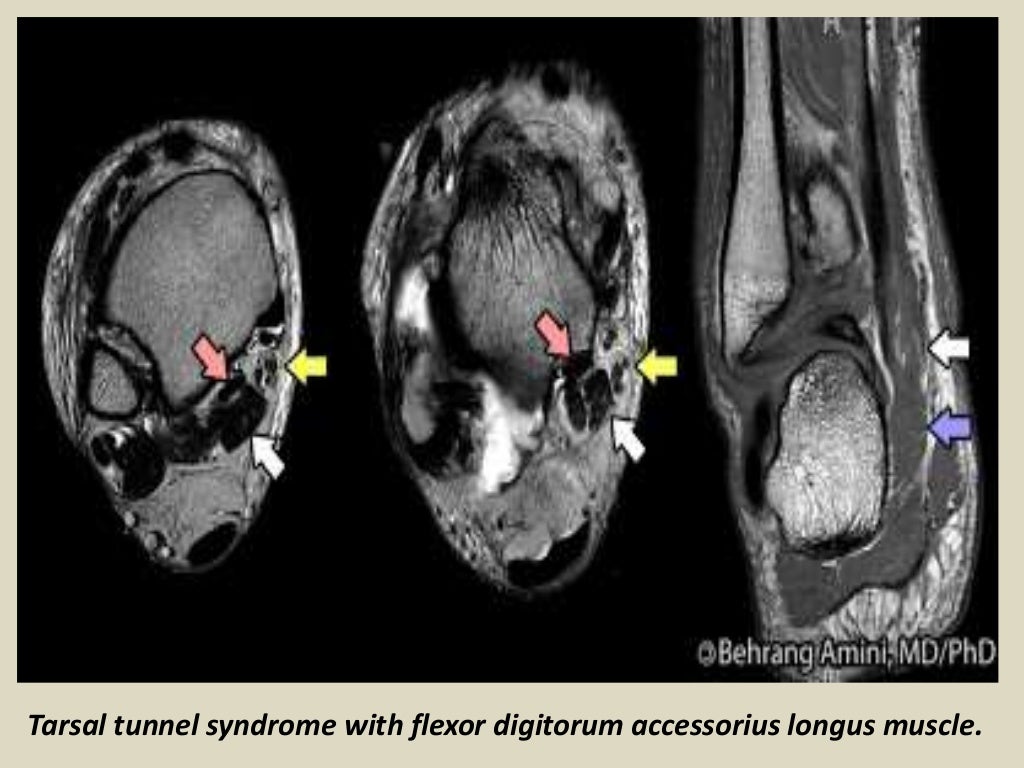

Presentation1 radiological imaging of tarsal tunnel syndrome. Tarsal Tunnel Syndrome X Ray Tarsal tunnel syndrome (tts) is a common entrapment syndrome whose diagnosis can be difficult. Tarsal tunnel syndrome refers to an entrapment neuropathy (tunnel syndrome) of the (posterior) tibial nerve or of its branches within the tarsal tunnel. Mr imaging can accurately depict the contents of the tarsal tunnel and the courses of the terminal branches of the posterior tibial nerve.. Tarsal Tunnel Syndrome X Ray.

Presentation1 radiological imaging of tarsal tunnel syndrome. Tarsal Tunnel Syndrome X Ray Tarsal tunnel syndrome is a compressive neuropathy of the tibial nerve at the level of the tarsal tunnel which can lead to pain. This condition is analogous to carpal tunnel. Tarsal tunnel syndrome refers to an entrapment neuropathy (tunnel syndrome) of the (posterior) tibial nerve or of its branches within the tarsal tunnel. Tarsal tunnel syndrome refers to an entrapment. Tarsal Tunnel Syndrome X Ray.

Presentation1 radiological imaging of tarsal tunnel syndrome. Tarsal Tunnel Syndrome X Ray Tarsal tunnel syndrome refers to an entrapment neuropathy (tunnel syndrome) of the (posterior) tibial nerve or of its branches within. Mr imaging can accurately depict the contents of the tarsal tunnel and the courses of the terminal branches of the posterior tibial nerve. Tarsal tunnel syndrome (tts) is a common entrapment syndrome whose diagnosis can be difficult. This condition is. Tarsal Tunnel Syndrome X Ray.

Presentation1 radiological imaging of tarsal tunnel syndrome. Tarsal Tunnel Syndrome X Ray This condition is analogous to carpal tunnel. Mr imaging can accurately depict the contents of the tarsal tunnel and the courses of the terminal branches of the posterior tibial nerve. Tarsal tunnel syndrome refers to an entrapment neuropathy (tunnel syndrome) of the (posterior) tibial nerve or of its branches within the tarsal tunnel. Tarsal tunnel syndrome refers to an entrapment. Tarsal Tunnel Syndrome X Ray.